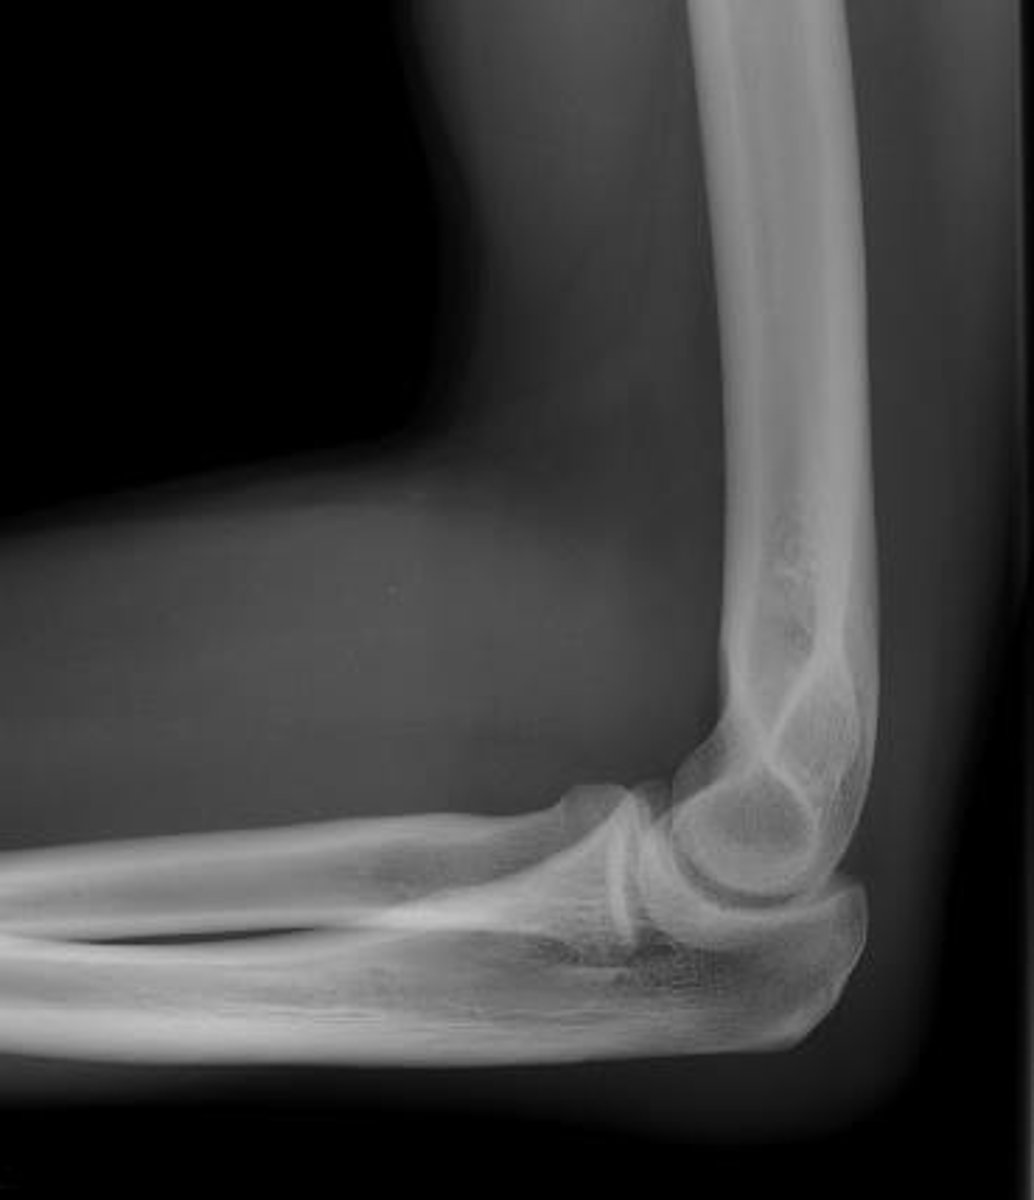

Ex: Elbow

Example of an articulation involving the Humerus and Ulna, and Humerus and Radius.

<p>Example of an articulation involving the Humerus and Ulna, and Humerus and Radius.</p>

Coronoid Fossa

Anterior-medial depression for coronoid process of ulna

Olecranon Fossa

Posterior depression for olecranon process of ulna

Trochlear Notch

articulates with trochlea of humerus

Olecranon Process

prominent posterior bump

Coronoid Process

inferior lip of trochlear notch